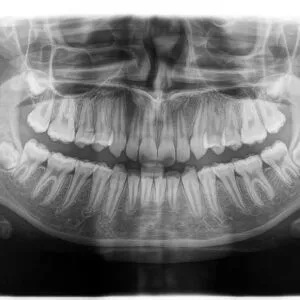

An Orthopantomogram x-ray (OPG x-ray) is a wide-view, panoramic x-ray of the patients upper and law jaw, and associated dentition from root to crown, in a single image – which is not possible with periapical or Bite-wing x-rays.

A digital OPG x-ray is especially helpful in planning of orthodontic dental brace treatment, as it provides a full overview of the teeth, and highlights non-erupted and/or impacted teeth.